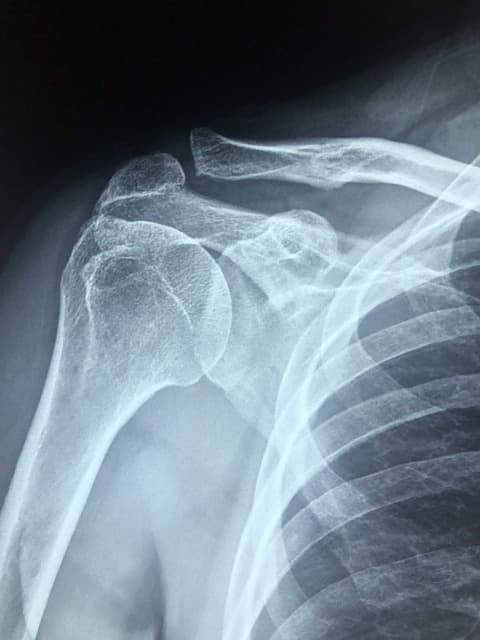

조용히 진행되는 뼈 손실은 나중에 골절이나 척추 손상, 관절 통증 등으로 나타나며, 점차 회복이 쉽지않습니다.